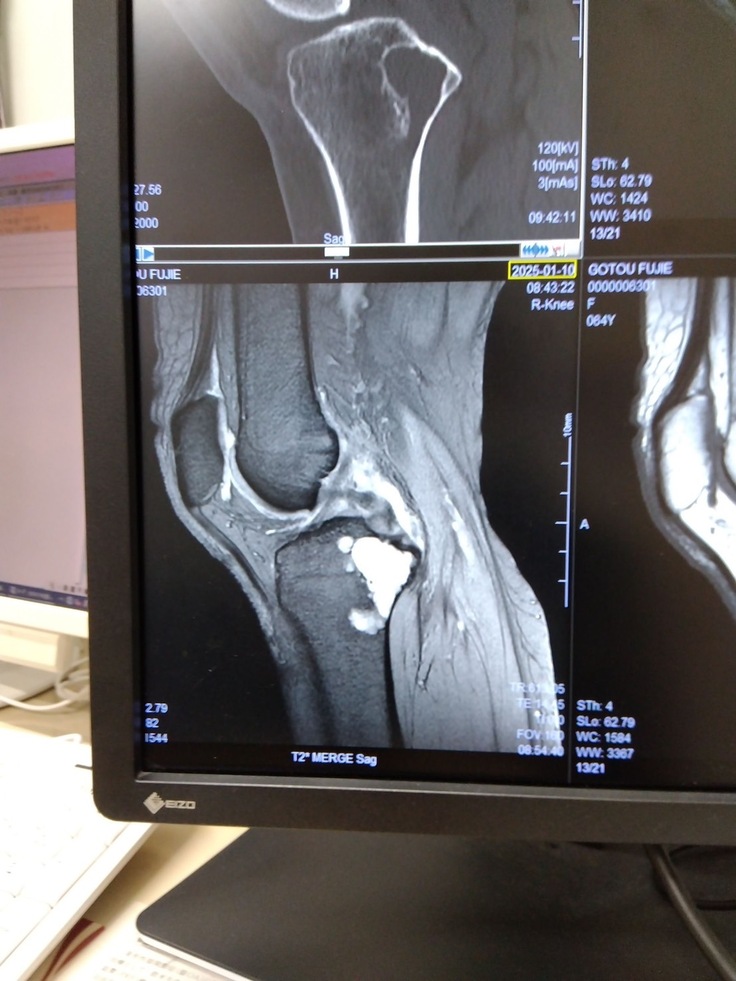

そして今回、病院の受診時に脛骨部分(足の骨)に腫瘍があることがわかりました。

背骨の変形も見られるのですが、骨腫瘍が特にひどく、このまま放置すると歩けなくなると言われ手術、入院をする運びになりました。

腫瘍自体はまだ良性か悪性か不明なため、手術して除去する際に細胞の検査を行い診断する流れになります。